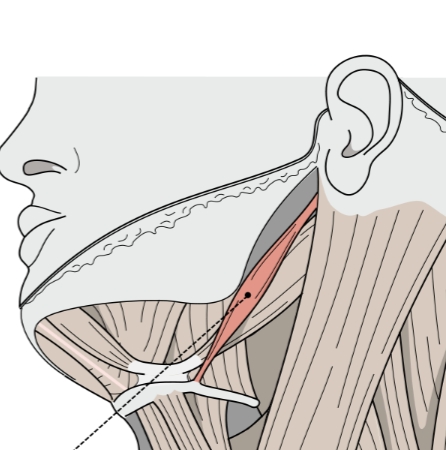

What is this muscle?

Stylohyoid (elevate.retract hyoid)

What is this muscle?

Thyrohyoid (depress hyoid, elevate larynx)

What is this muscle?

Sternohyoid (depress hyoid)

What is this muscle?

Omohyoid (depress hyoid)

What is this muscle?

Sternothyroid (depress thyroid)